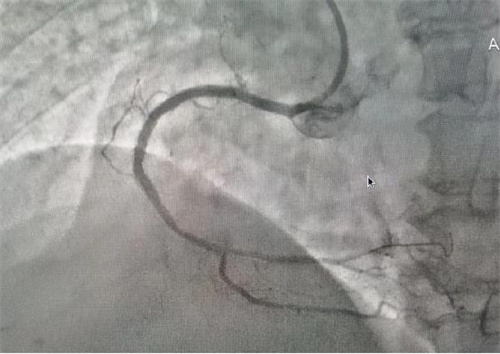

據(jù)了解,此次順利完成經(jīng)皮冠狀動脈內(nèi)支架植入術的患者共有4位,其中一名68歲老年女性患者,因胸悶氣促6余年,活動后明顯加重入院治療。經(jīng)冠脈造影檢查,發(fā)現(xiàn)左前降支次全閉塞、右冠99%重度狹窄,三支血管重度病變,情況危急。經(jīng)病情評估后,與患者家屬溝通,決定立即對右冠實施冠狀動脈球囊擴張加支架植入術。在上級專家的指導下,心病科團隊成功擴張了狹窄血管、植入支架,手術順利,患者術后安返病房,為患者后續(xù)治療創(chuàng)造了有力條件。